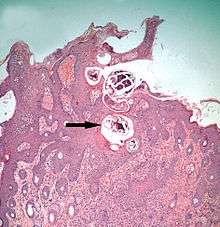

- Psoroptic mites feed superficially at the stratum corneum. The photograph of a histological section of skin infested with Psoroptes ovis, and the photograph of the surface of a host's skin infested with P. ovis looking like white dots, show this type of feeding.

The clinical manifestation of infestation with psoroptic mites is usually called mange and sometimes scabies, but the skin disease of sheep caused by Psoroptes ovis is often known locally as sheep scab. This species may affect its hosts severely enough to reduce their gain in weight.[25] Costs to farmers of controlling sheep-scab in Britain were at £8 million (US$12 million) annually in 2005.[26] Transmission between hosts is readily accomplished by contagion during flocking contact and also on fomites such as scraps of sheep's wool because these relatively large and robust mites can survive for one to two weeks off their host. Psoroptes ovis infests the superficial layers of the skin. Irritation of the outer skin by the mite's mouthparts and saliva results in a complex form of cutaneous hypersensitivity and inflammatory exudation of serum and fresh cells. The mites feed on this moist exudate.[27] The skin loses its hair (depilation) at the sites of infestation and this may be extensive. As a result of the movement of the mites into areas of fresh skin, large scabs accumulate on the raw skin left behind. The mites cause intense pruritus (itching). In cases of heavy infestations, the host grooms compulsively, aggravating the depilation, and it may become mentally distressed.[28] Psoroptes ovis infests sheep worldwide and can be a serious welfare and animal-production problem for sheep farmers. Infestations of cattle with mites of the similar genus Chorioptes, in combination with Sarcoptes mite infestation, has been shown to cause a failure to gain body weight by 15.5 kg to 37.2 kg over a two-month period compared to cattle without the mites.[29]